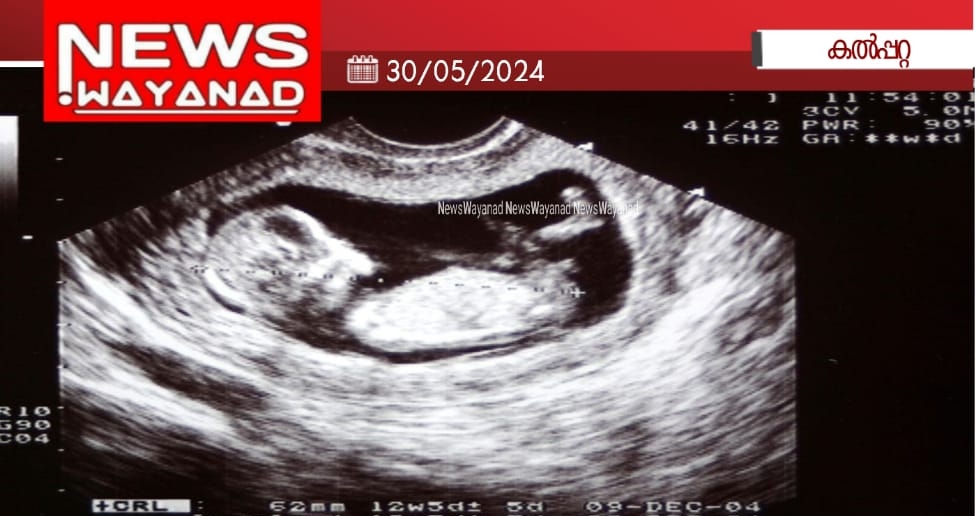

ഗർഭസ്ഥശിശുവിന്റെ ലിംഗനിർണയം: സ്കാനിങ് കേന്ദ്രങ്ങളിൽ പരിശോധന

കൽപ്പറ്റ: ഗർഭസ്ഥശിശുവിന്റെ ലിംഗനിർണയവുമായി ബന്ധപ്പെട്ട് പി.സി. ആൻഡ് പി.എൻ.ഡി.ടി. നിയമപ്രകാരം ജില്ലയിലെ സ്കാനിങ് കേന്ദ്രങ്ങളിൽ പരിശോധന നടത്തും. കളക്ടർ ഡോ. രേണുരാജിന്റെ അധ്യക്ഷതയിൽ ചേംബറിൽ ചേർന്ന പി.സി. ആൻഡ് പി.എൻ.ഡി.ടി. ജില്ലാതല ഉപദേശകസമിതി യോഗത്തിലാണ് തീരുമാനം. പൊതുയിടങ്ങൾ, ആശുപത്രികൾ, സ്ഥാപനങ്ങൾ കേന്ദ്രീകരിച്ച് പി.സി. ആൻഡ് പി.എൻ.ഡി.ടി. നിയമബോർഡുകൾ സ്ഥാപിക്കാനും യോഗത്തിൽ ആവശ്യമുയർന്നു.

സുൽത്താൻബത്തേരി ഇഖ്റ ആശുപത്രിയുടെ രജിസ്ട്രേഷൻ പുതുക്കിനൽകാൻ യോഗം തീരുമാനിച്ചു. സ്കാൻ ചെയ്യാനെത്തുന്നവർക്ക് പി.സി. ആൻഡ് പി. എൻ.ഡി.ടി. നിയമപ്രകാരമുള്ള സൗകര്യങ്ങൾ സ്ഥാപനത്തിൽ ഉറപ്പാക്കണം. ഗർഭസ്ഥശിശുവിന്റെ ലിംഗത്തെ സൂചിപ്പിക്കുന്ന ചിഹ്നങ്ങൾ, നിറങ്ങൾ എന്നിവ പ്രദർശിപ്പിക്കാനും പാടില്ല.